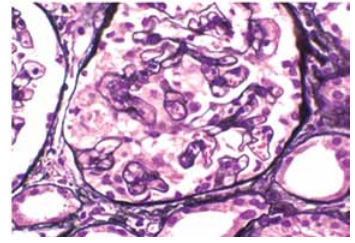

Submetida à biópsia renal: cortical representada por 28 glomérulos, 15 glomérulos apresentam hiperplasia podocitária segmentar e colapso parcial ou global de alças capilares. O restante deles tem a estrutura geral preservada, com celularidade normal, capilares com luz patente e membrana basal sem alterações significativas. As cápsulas de Bowman estão íntegras.

(Coloração de prata de Jones. Disponível em: https://www.ajkd.org)

A opção diagnóstica que melhor justifica o caso é: